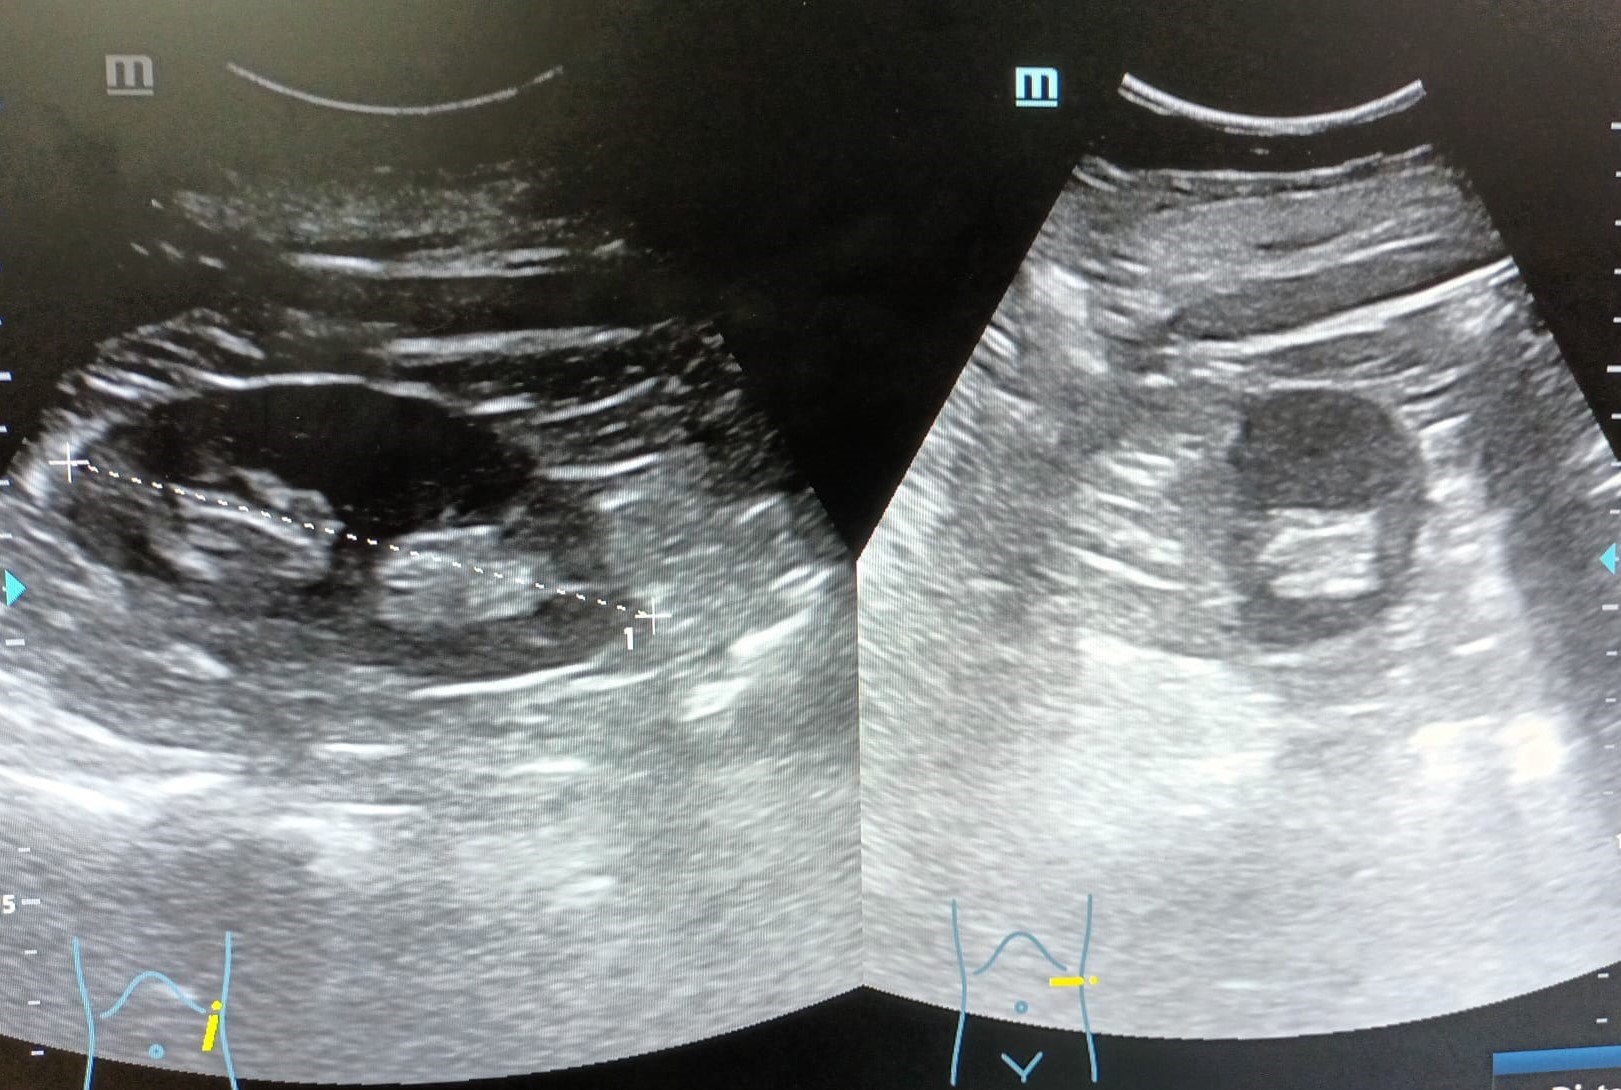

Ambos riñones de tamaño (derecho 99,7 mm e izquierdo 112,6 mm de longitud cráneo-caudal) y localización normal, con buena diferenciación corticomedular, sin lesiones ocupantes de espacio ni imágenes litiásicas en su interior, sin signos de uropatía obstructiva.

Vejiga: lesión hiperecogénica, de bordes bien definidos, adherida a pared, en zona del trígono vesical, colindante con uréter izquierdo, que no capta Doppler, de aproximadamente 4,2 x 6,7 mm.